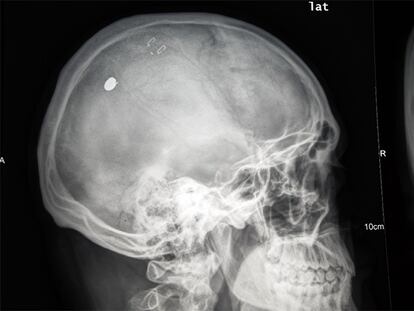

Radiografía del cráneo de M. P. D.

A perdigonadas en Vallecas

La policía busca a un tirador que hirió a cinco personas